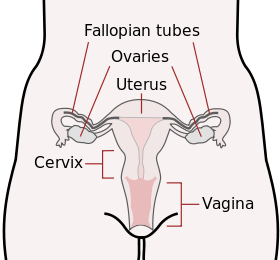

Diagram of the female human reproductive tract and ovaries | |

The vagina is a muscular and tubular part of the female genital tract, which in humans extends from the vulva to the cervix. The outer vaginal opening may be partly covered by a membrane called the hymen. At the deep end, the cervix (neck of the uterus) bulges into the vagina. The vagina allows for sexual intercourse and childbirth, and channels menstrual flow, which occurs periodically as part of the menstrual cycle.

The human vagina develops into an elastic muscular canal that extends from the vulva to the cervix.[12][13] It is reddish pink in color, and it connects the superficial vulva to the cervix of the deep uterus. The vagina is behind the urethra and bladder, and reaches across the perineum superiorly and posteriorly toward the cervix; at approximately a 90 degree angle, the cervix protrudes into the vagina.[14] The vaginal orifice and urethral opening are protected by the labia.[15]